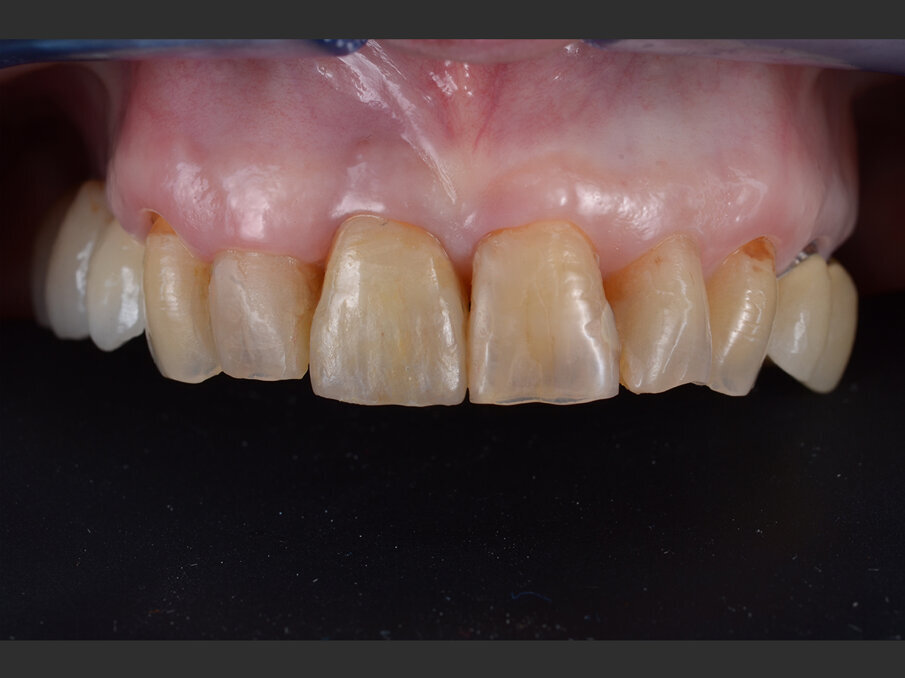

La paziente, donna di 60 anni, non fumatrice ed in buone condizioni di salute generale, si presenta in studio con sintomi di pulpite irreversibile a carico dell’elemento 1.1. L’esame clinico (Figg. 1a, 1b) e radiografico (Fig. 2a) confermano la presenza di una lesione cariosa radicolare che ha colpito il versante mesiale.

Fig. 1a - Valutazione pre-operatoria - visione frontale: l’elemento 1.1 è sintomatico e mostra segni e sintomi di pulpite irreversibile.

Fig. 1b - Valutazione pre-operatoria - visione palatina: è possibile apprezzare la lesione cariosa corono-radicolare.